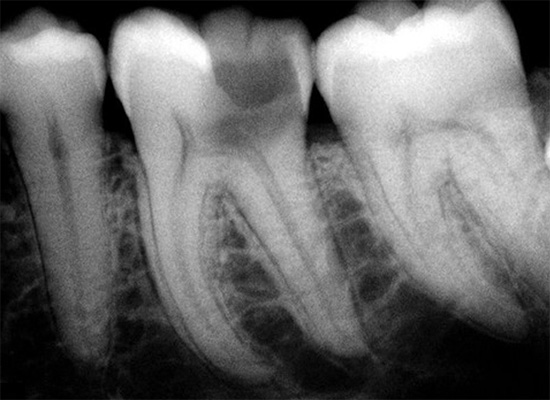

Utilizzando i metodi di ricerca a raggi X, è possibile stabilire la gravità del processo carioso e il livello delle sue complicanze. Possono esserci varie manifestazioni di infiammazione alla radice e la loro evidente presenza negherà la diagnosi di carie dentinale.

A volte la carie della dentina è mascherata dalle sue complicanze (ad esempio, da forme croniche di pulpite o parodontite). Sfortunatamente, in situazioni così insolite, i sintomi possono essere simili in alcuni aspetti. Solo un dentista all'appuntamento può finalmente determinare la diagnosi.